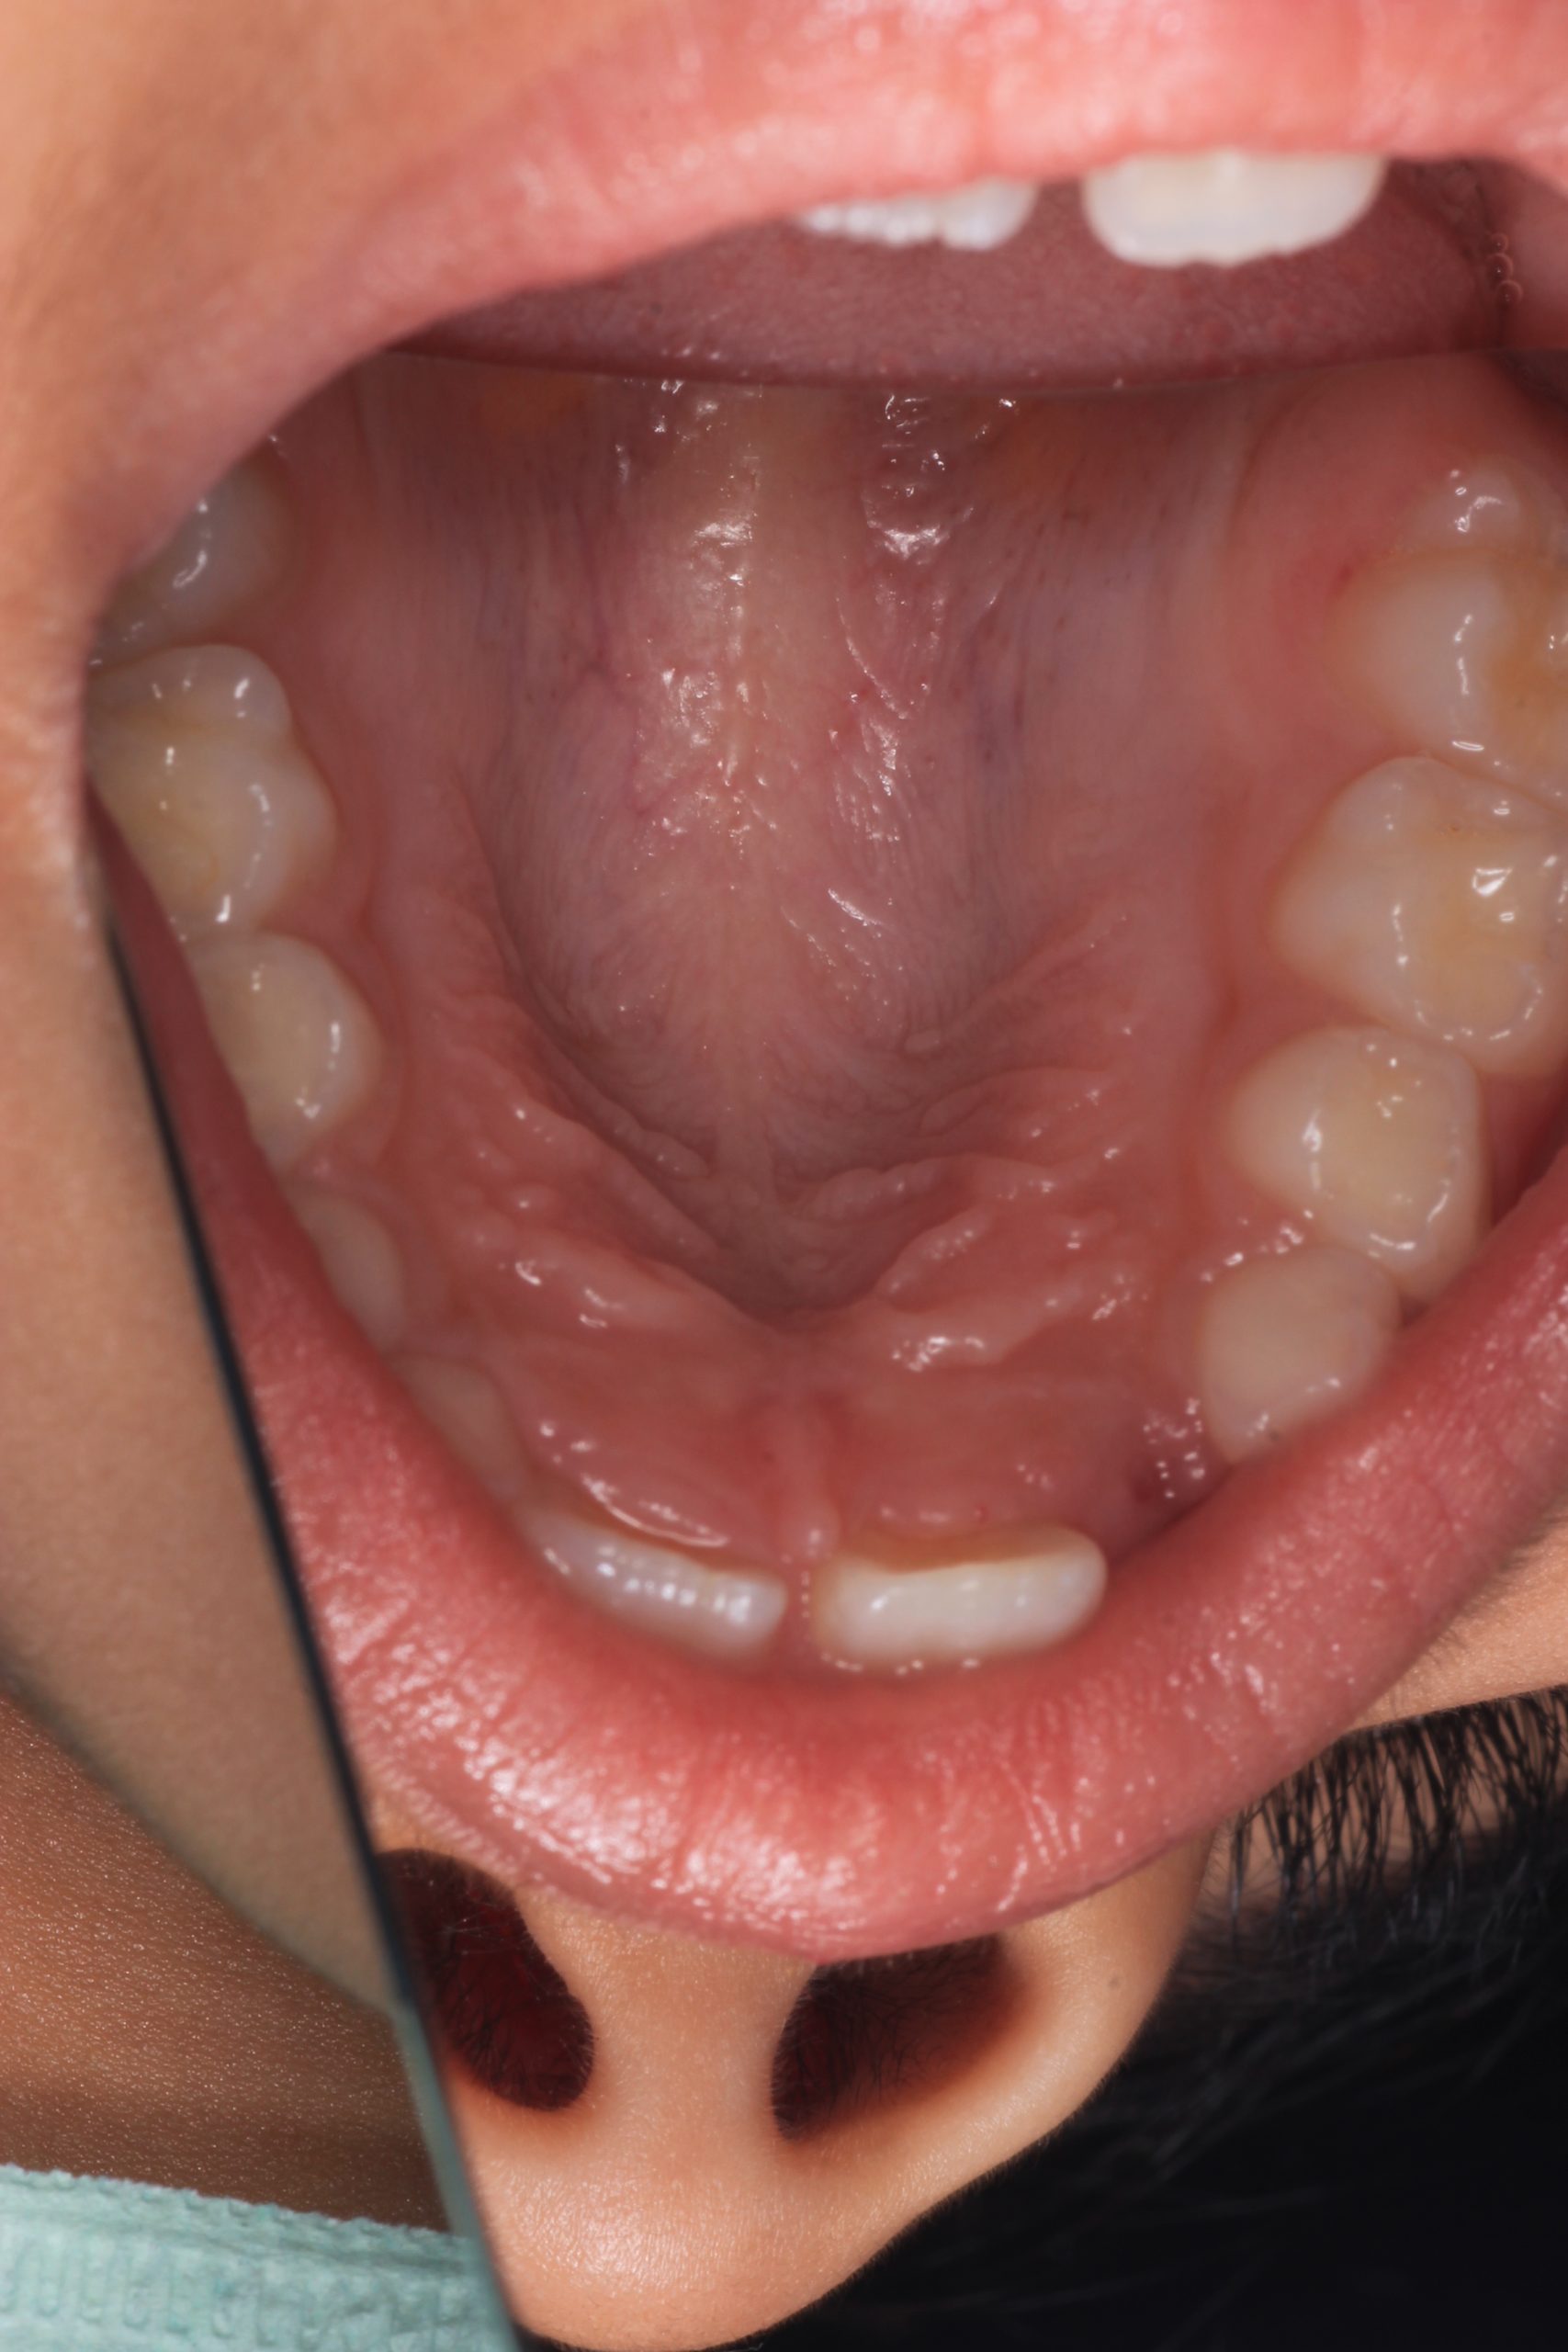

As early as the child allows it. Home care should begin even before the first tooth erupts, and professional hygiene can start as soon as the first baby teeth appear.

- For toddlers under 4, we provide gentle hygiene using soft rubber polishing brushes and a special tasty professional paste designed for children.

- From around age 4–5, when the child is ready, we can perform a full AirFlow cleaning using the GBT protocol.